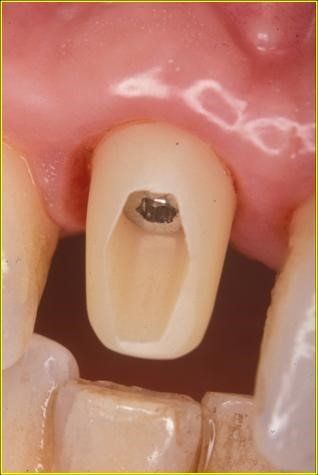

Nel 1994 una paziente di 28 anni subì la frattura dell’incisivo centrale superiore sinistro precedentemente trattato endodonticamente

Un caso analogo al precedente.

Una giovane signora di ventotto anni subisce nel 1996 la frattura dell’incisivo centrale superiore destro

in precedenza trattato endodonticamente